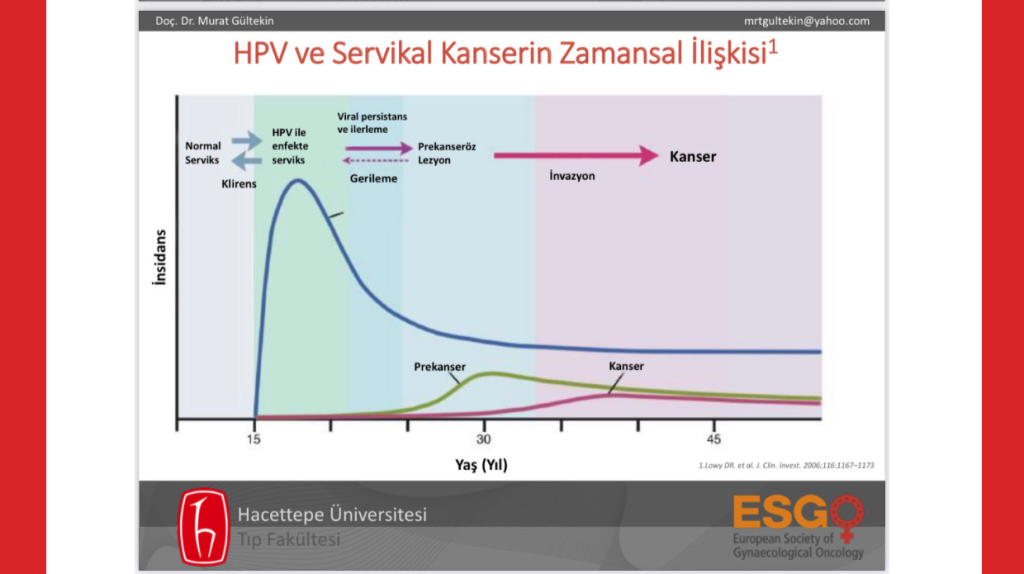

Sağlık Bakanlığı Halk Sağlığı Genel Müdürlüğü’nün sitesinde hala bulunan “HPV Aşıları” adlı sunumda8 “HPV ve Servikal Kanserin Zamansal İlişkisi” grafiğinde HPV enfeksiyonun 18 yaşında zaten pik yaptığı görülüyor. Yukarıda da bahsettiğim üzere “bir kadının ilk cinsel deneyiminde HPV enfeksiyonu geçirmesinin kümülatif riskinin %46” olduğunu biliyoruz. Yani Bakan, enfeksiyonun arşa çıktığı yaş aralığına öncelik verip, öncesi yaşlardaki çocuklara aşı hakkını sunmayarak akıl kârı olmayan bir tercihte bulunmuş oluyor. Oysa koruyucu özellikteki aşı tam da bu nedenle cinsel yaşam aktif değilken çocuk yaşta yapılması gerekiyor.